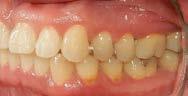

Se presenta una paciente clase ll esquelética en los estudios extrao rales en la fotografía de frente se ve hiperdivergente con una mordi da profunda de 5mm, un diastema, y refiere como motivo de consulta "no me gusta el espacio entre mis dien tes" (Figura 1).

En los estudios intraorales de inicio en las fotografías se muestra en la de frente el diastema anterior, con la línea media dental superior e inferior no coincidentes, la mordida profun da anterior (Figura 2), en la lateral derecha clase l molar y canina bila teral (Figura 3), el apiñamiento leve superior e inferior y la forma de las arcadas.